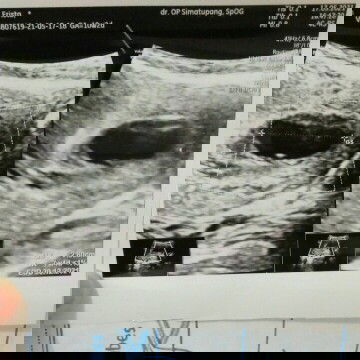

Akhirnya kuretasi setelah mengandung 10week. sedih memang. Karena selama kehamilan ternyata mengalami hamil BO. Pernikahan saya sudah 2 bulan. Moms doakan yah semoga saya bisa hamil kembali dengan kondisi kehamilan lancar, sehat semuanya Jadi saya waktu lalu, periksa usg dan dinyatakan kondisi hamil Bo, lalu seminggu lagi jika tdk ada perkembangan akan dikuretasi. Pengalaman kuretasi, saya datang ke RSIA jam10 memakai BPJS dan dan harus rapid antigen, kemudian diigd, lalu ruang bersalin. Alat kelaminnya dimasukan alat rasanya sakit banget. Ditambah tambahan suntikan. Kemudian dibius total dan jam stgh 6 saya dikuretasi. Rawat inap. Kemudian besoknya sudah tdk terasa. Seperti haid biasa. Dan jam 10 saya pulang.#bantusharing #jangandibully #firstbaby